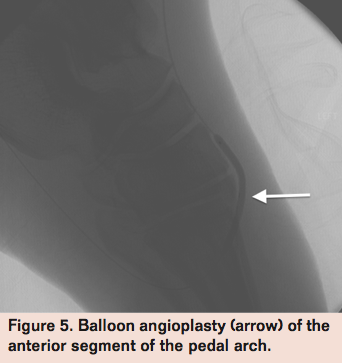

A 2.5 x 60 mm Amphirion balloon (Medtronic) was used to predilate the lesion at 18 atm (Figure 5) for 3 minutes. Final angiogram revealed brisk flow through the entire plantar arch feeding the anterior and posterior tibial arteries (Figure 6).